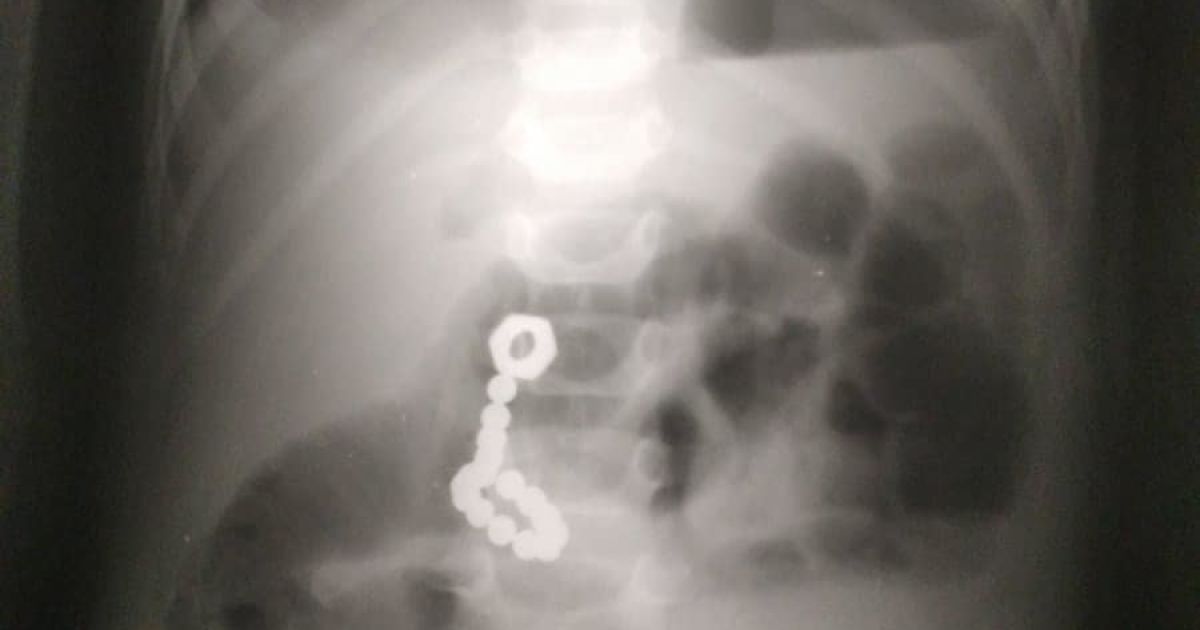

Смертельная авария на въезде в Днепр — мужчина перебегал трассу, когда его на полной скорости сбил легковой автомобиль.

Удар был такой силы, что пешеходу оторвало ногу, мужчина погиб на месте.

Пешеходного перехода, где проходил погибший, на этом участке трассы нет. Более того, там стоит отбойник, разделяющий встречные полосы движения. В двух сотнях метров есть светофор, пешеход решил сэкономить время и не идти к нему.